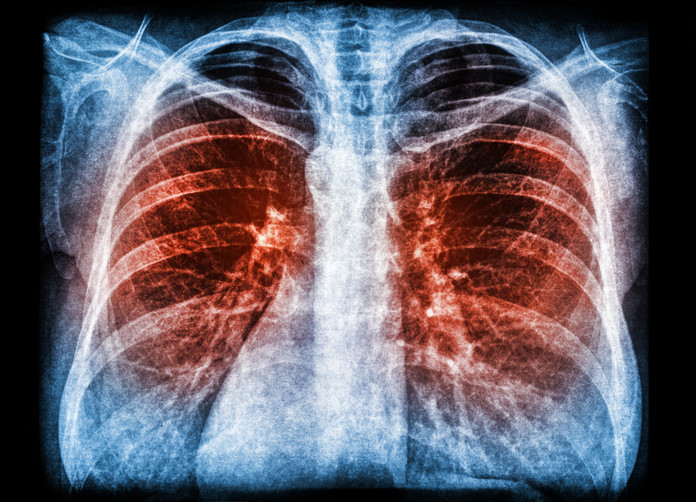

KOAH, hava kesecikleri olan bronşların daralması sonucu akciğerde elastikiyet kaybı, nefes darlığı, öksürük ve hava akımının kısıtlanması ile ortaya çıkan kronik inflamatuar bir akciğer hastalığıdır. KOAH, amfizem ve kronik obstrüktif bronşiti de içerir.

KOAH tüm vücut sistemini olumsuz etkileyen önemli bir hastalıktır. Akciğer yaşlanmasını hızlandırmaktadır. Diyabet, kemik erimesi, kalp damar tıkanıklıkları ve kaslarda enfeksiyon dışı iltihaplar gibi sorunlar KOAH ile birlikte görülebilmektedir.